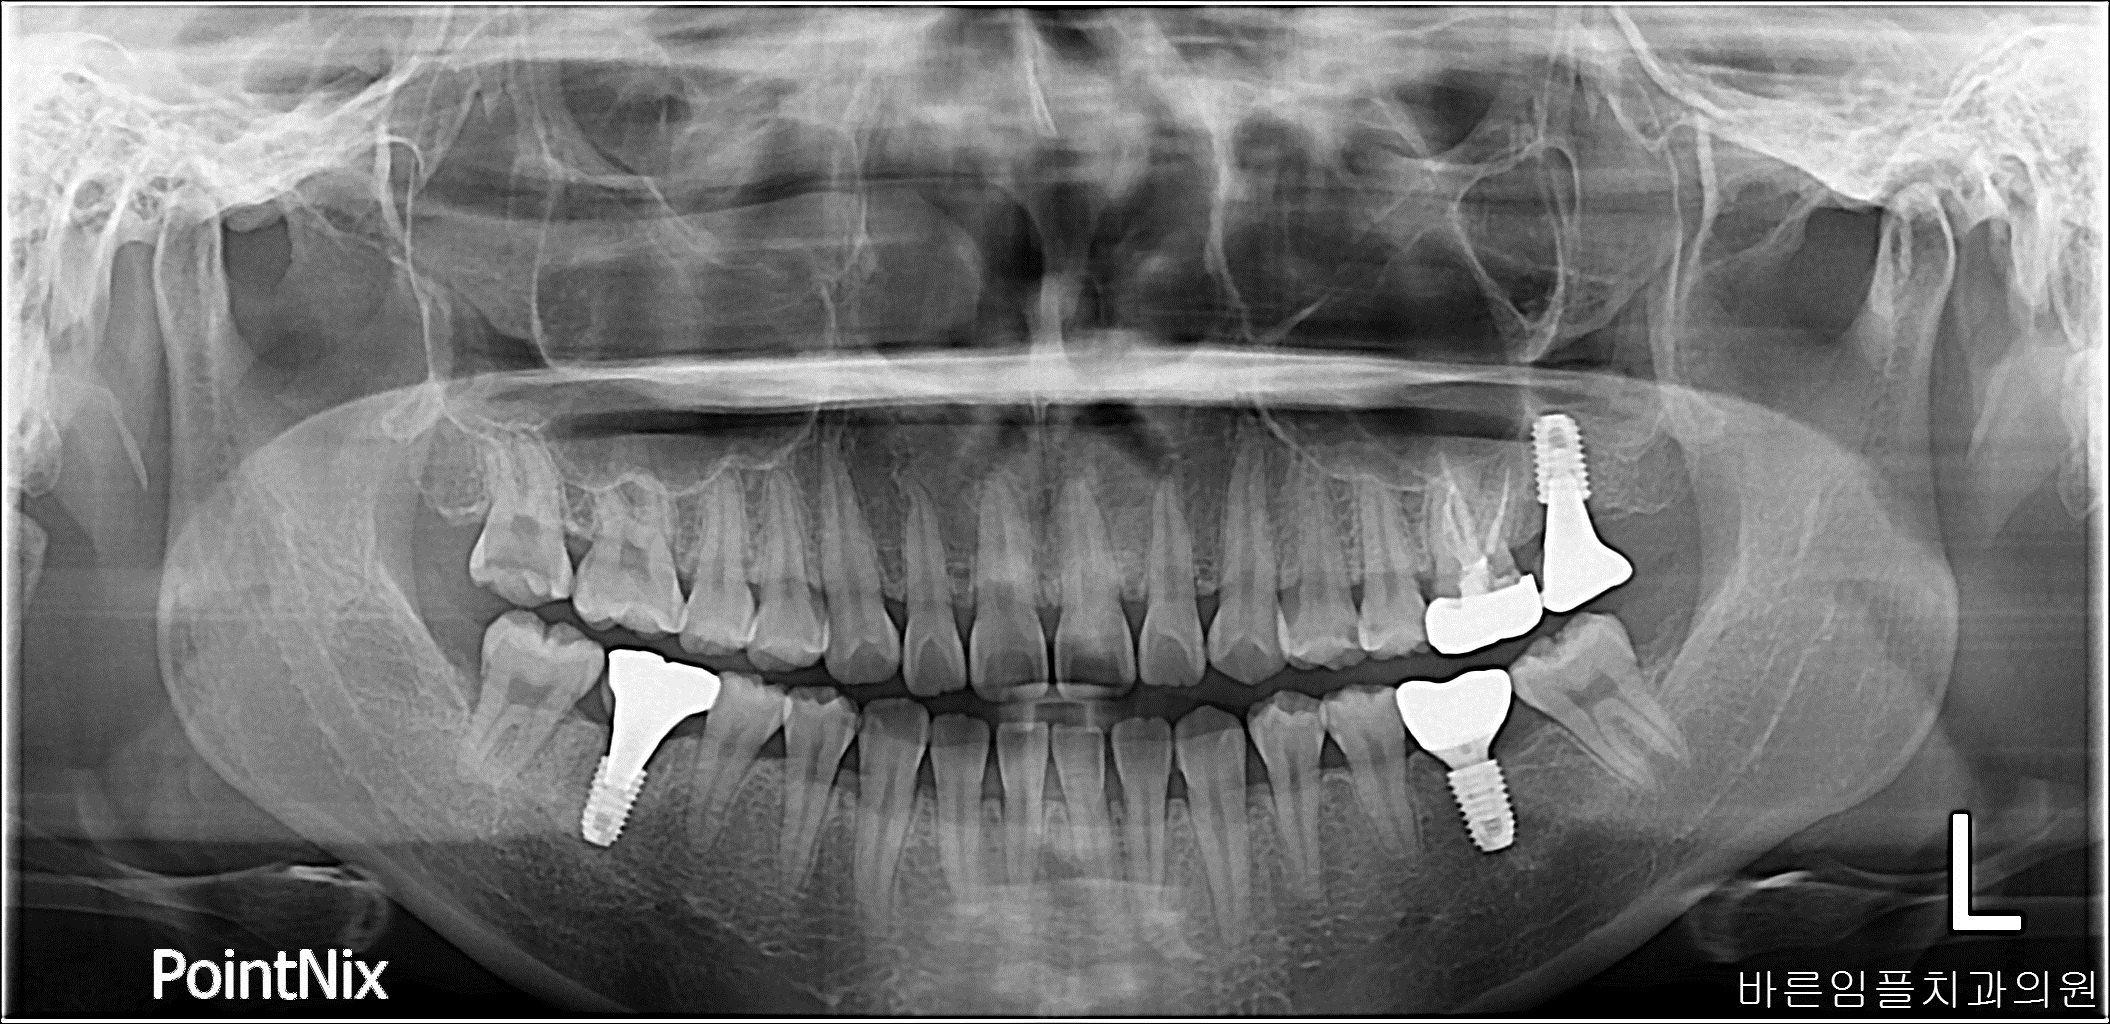

남ㅇㅇ / 임플란트 페이지 정보 작성일 23-10-27 17:02 2022-10-01 남ㅇㅇ Before 2023-09-02 남ㅇㅇ After 남ㅇㅇ / 임플란트 목록 이전글박ㅇㅇ / 수면임플란트 다음글 김ㅇㅇ / 수면임플란트